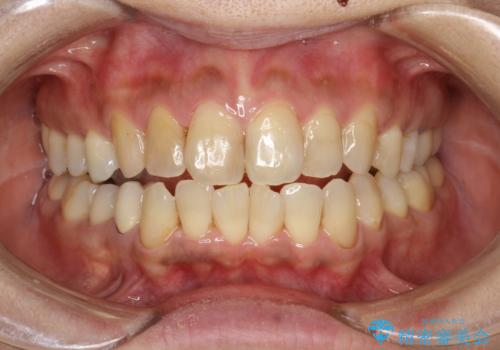

歯と歯の間の着色除去

- 着色が歯と歯の間や、詰め物との境目に多い患者様。

細かい部分まで届くようにエアフローにて施術しました。

施術コース:エアーフロー60分コース 12000円

詰め物との境目の汚れは、ポリッシングブラシでは取り除くことが難しいため

エアフローの細かいパウダーを角度を変えて当ててとれる範囲で除去しました。